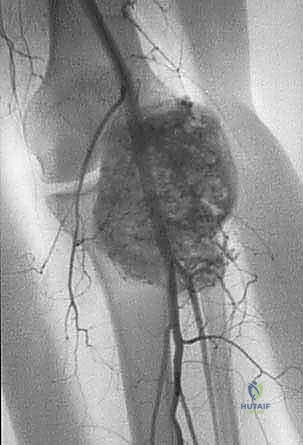

- الرنين المغناطيسي (MRI): هو المعيار الذهبي (Gold Standard) لتقييم الأورام. يوضح بدقة امتداد الورم في النخاع العظمي والأنسجة الرخوة، وعلاقته بالأعصاب والأوعية الدموية.

- الأشعة المقطعية (CT Scan): ضرورية لتقييم القشرة العظمية والتكلسات داخل الورم، وللبحث عن أي انتشار في الرئتين.

الحالة الأولى: إنقاذ ركبة رياضي شاب

شاب يبلغ من العمر 19 عاماً عانى من ألم مستمر في الركبة وتورم لم يستجب للمسكنات. بعد الفحص السريري الدقيق وإجراء الرنين المغناطيسي، اشتبه الأستاذ الدكتور محمد هطيف بوجود ورم. تم إجراء خزعة إبرة أساسية دقيقة جداً. أظهرت النتائج وجود "ساركوما عظمية" في مراحلها الأولى. بفضل الخزعة الدقيقة التي لم تلوث الأنسجة المحيطة، تمكن الدكتور هطيف لاحقاً من استئصال الورم بالكامل وتركيب مفصل صناعي خاص بالأورام، مما أنقذ ساق الشاب من البتر ومكنه من العودة للمشي بشكل طبيعي.